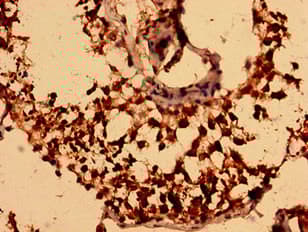

Rabbit Polyclonal NEGR1 antibody. Suitable for WB, IHC-P, ICC/IF and reacts with Human samples. Cited in 1 publication. Immunogen corresponding to Recombinant Fragment Protein within Human Neuronal growth regulator 1 aa 1-200.

Applications ICC/IF, IHC-P, WB